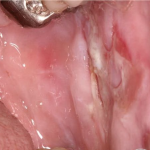

Pemphigus Mucosae = فقاع الاغشية المخاطية